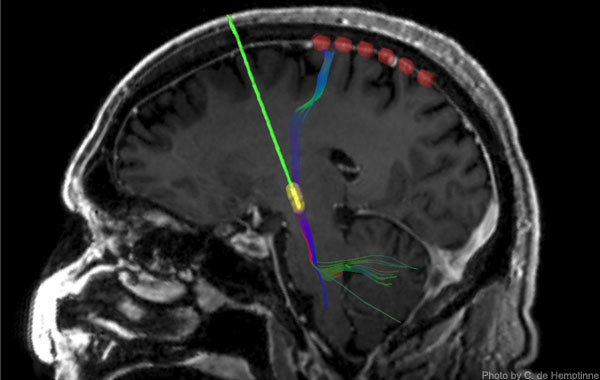

During surgery on 23 patients with Parkinson’s disease in whom permanent DBS electrodes were being surgically implanted, the UCSF team slid a temporary strip of six recording electrodes under the skull and placed it over the motor cortex. As in the prior research, recordings of neural activity showed excessive synchronization of activity rhythms in the patients.

As the name of the therapy implies, the ends of the stimulating leads of DBS devices are placed in a structure deep in the brain known as the subthalamic nucleus (STN), which is part of a “loop” of neural circuitry that includes the motor cortex on the brain’s surface. When the DBS device was activated and began stimulating the STN, the effect of the stimulation reached the motor cortex, where over-synchronization rapidly diminished. If the device was turned off, excessive synchrony re-emerged, more gradually in some patients than others.

DBS surgery generally takes about six hours, and during the middle of the procedure patients are awakened for testing of the device and to ensure that the stimulating lead is properly placed in the STN. During this period the researchers asked 12 of the patients to perform a reaching task in which they had to touch a blue dot appearing on a computer screen. Importantly, said Starr, recordings revealed that DBS eliminated excessive synchrony of motor cortex activity and facilitated movement without altering normal changes in brain activity that accompany movements.